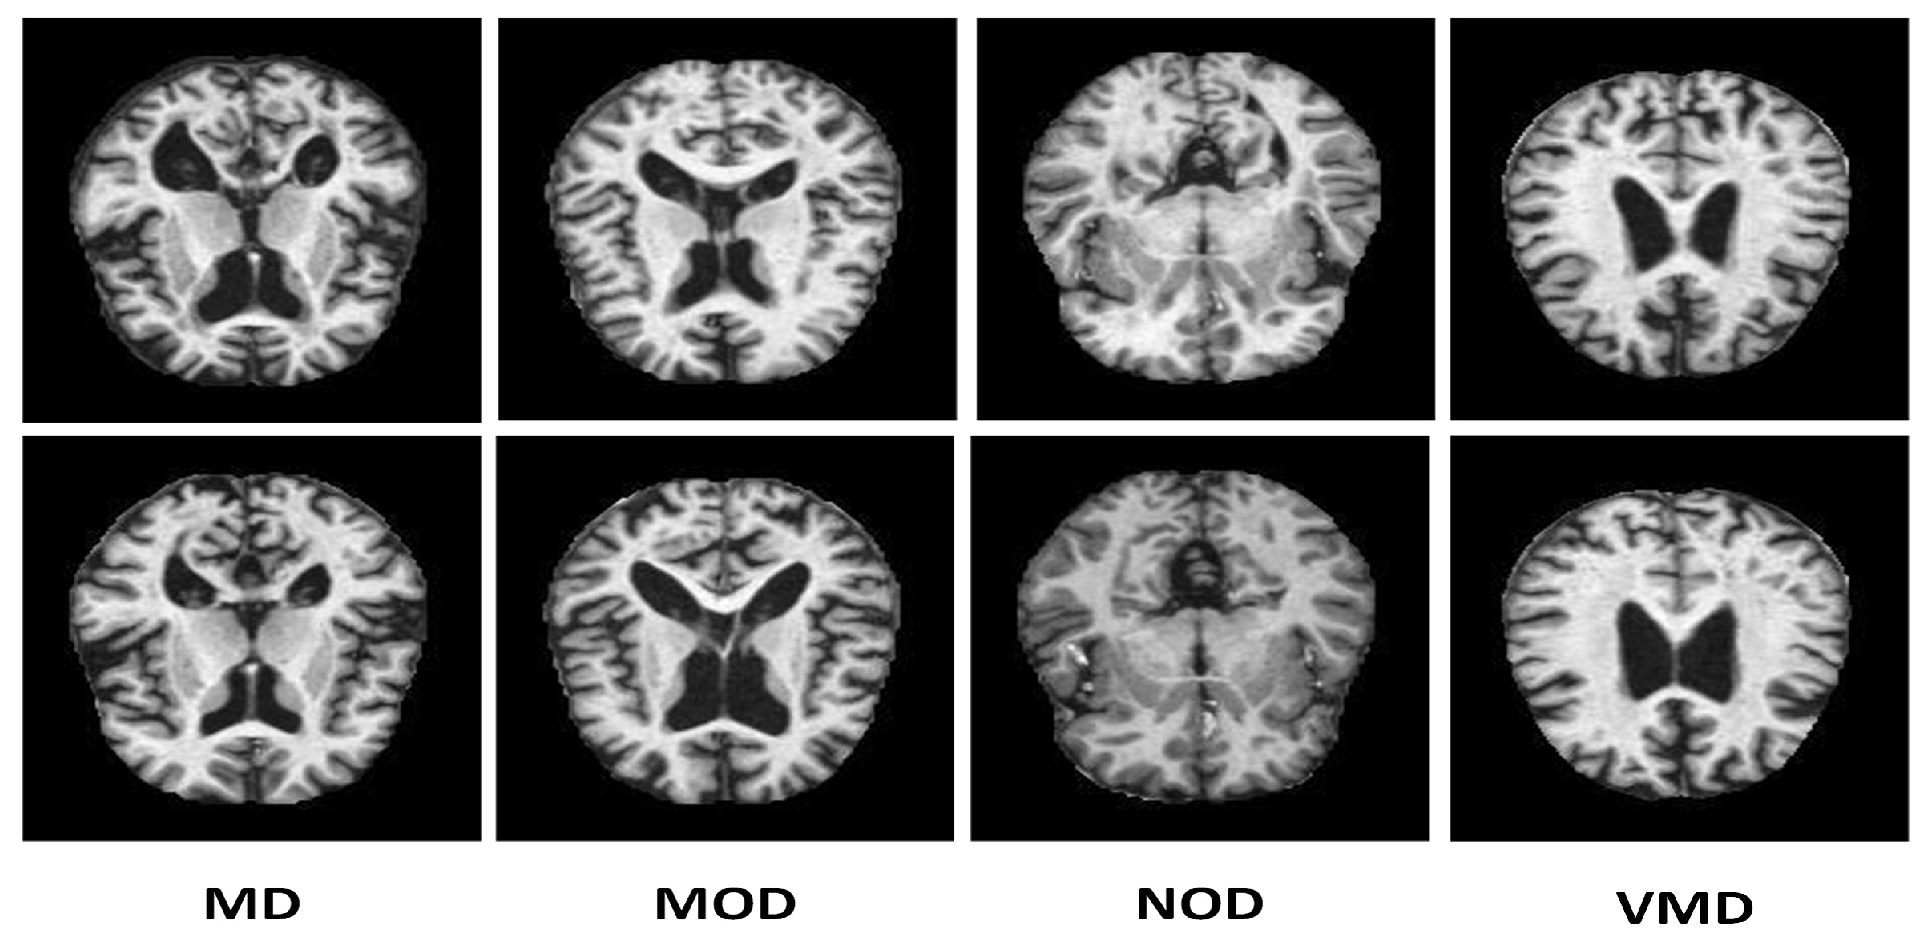

Many online data sets can be used to categorize AD properly. Organizations like ADNI and OASIS are working hard to ensure that researchers and educators have access to these data sets. However, the samples in both of these datasets are presented as three-dimensional graphics, and the datasets themselves are massive. In perspective, the OASIS dataset occupies space of about 18 TB, while the size of ADNI datset is about 450 GB. Kaggle data collection was used for this study since it contains only samples of anonymized MRI scan images and their associated classifications. This dataset is multiclass since it has four categories and many perspectives. A typical NOD group with three other groups representing the premature stages of Alzheimer’s disease (MD, MOD, and VMD) is shown in Figure 2.

As stated in the Kaggle’s dataset description, every representative sample has been manually verified by the user. Furthermore, the parts have already been cleaned up, that is, downsized and arranged, and the scale of the data set is manageable. The dataset shows precision of 2 decimal points [76]. Several other studies used this dataset with this precision for analysis [77]. This data collection is utilized in our study based on these variables. There are 6400 total samples in the data set. The examples are separate 176 x 208-pixel RGB three-channel images from four different classes. The NOD class consists of 3200 pieces. There are 896, 64, and 2240 photos in the last three classes, MD, MOD, and VMD, respectively. The imbalance in this data collection, which is explained in Table 2 is its only drawback. To address this problem, we used SMOTE to produce fictitious data, for each imbalance class with regards to the balanced type as displayed in Figure 2. Splitting of the dataset into training, validation, and test sets was made with proportions of 80%, 10%, and 10%, respectively.

Figure 2. Images taken directly from the AD data set using SMOTE without any up-sampling.